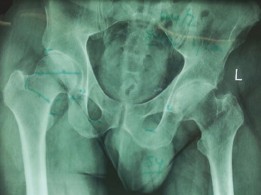

Standard preoperative radiographs included an anteroposterior (AP) pelvis centered over the symphysis pubis with 15 degrees of internal rotation of the lower extremities to profile the femoral necks, alongside true lateral and Dunn lateral views of both hips.

The AP Pelvis radiograph demonstrated severe, bilateral tricompartmental joint space narrowing. The left hip exhibited complete obliteration of the superior and axial joint spaces with bone-on-bone articulation. Subchondral sclerosis was prominent bilaterally, accompanied by marginal osteophyte formation at the femoral head-neck junction and the acetabular rim. Large subchondral cysts (geodes) were visible in the superior weight-bearing dome of the left acetabulum.

The lateral view of the left hip confirmed the loss of sphericity of the femoral head, extensive anterior and posterior osteophytosis, and severe joint space collapse.

The lateral view of the right hip demonstrated similar but slightly less advanced degenerative changes, with marked loss of anterior joint space and reactive subchondral bone formation.